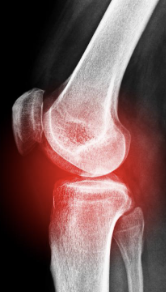

무릎 관절염 증상 원인 치료방법

무릎 관절염 증상 원인 치료방법 등 무릎 관절염과 관련된 정보를 알아보도록 하겠습니다. 무릎 관절염은 무릎 관절의 연골 파괴, 염증 및 변형으로 인해 발생하는 질환입니다. 증상으로는 통증, 감각 이상, 충동성 통증, 강직성 및 관절의 이상운동이 포함된다. 주요 위험 인자로는 노화, 비만, 골관절염, 부상 및 과도한 사용 등이 있습니다. 진단은 증상 및 영상진단 검사를 통해 이루어지며, 치료는 수술, 약물 치료, 생활습관 변화, 물리 치료 등이 있습니다. 무릎 관절염은 진행성이며, 조기 발견 및 치료가 중요합니다. 예방을 위해서는 체중 조절, 적극적인 운동, 관절 보호를 위한 적절한 신발 착용 등이 필요합니다.

무릎 관절염 증상

무릎 관절염 증상은 천천히 진행되며, 다음과 같은 증상이 나타납니다.

- 통증: 무릎 관절 주위에 통증이 나타나며, 장시간 서 있거나 앉아 있을 때 악화됩니다. 일부 사람들은 밤에도 통증을 느낄 수 있습니다.

- 관절 이상운동: 무릎 관절에서 뻐근함이나 강직함을 느낄 수 있습니다. 이러한 강직성으로 인해 보행이 어려워질 수 있습니다.

- 충동성 통증: 무릎을 갑자기 움직였을 때 발생하는 통증으로, 발작적인 통증이 나타납니다.

- 염증: 무릎 주위의 염증은 붓기와 따끔함을 유발합니다.

- 감각 이상: 무릎 관절에 통증과 함께 무릎 주위의 피부 감각이 변화할 수 있습니다.

이러한 증상이 지속되면 무릎 관절 염증의 진행을 막기 위해 적절한 치료를 받아야 합니다. 또한, 진행을 방지하기 위해 일상 생활에서 주의해야 할 부분이 있습니다.